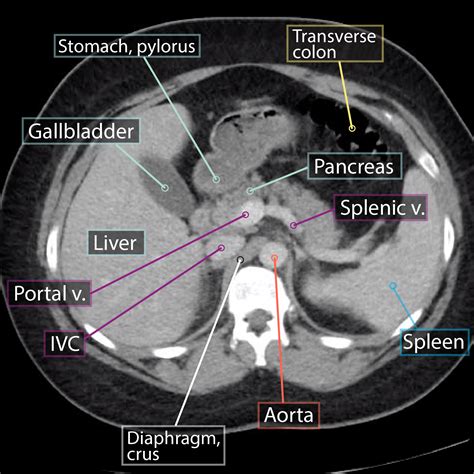

During the procedure, the patient lies on a table that slides into a doughnut-shaped machine. The machine rotates around the body, taking multiple X-ray images from different angles. These images are then processed by a computer to create cross-sectional views of the abdomen.

Interpreting Abdominal CT Normal Results

When an abdominal CT scan is performed, the radiologist reviews the images to identify any abnormalities. An abdominal CT normal result indicates that no significant abnormalities were detected. This means that the organs, tissues, and structures within the abdomen appear healthy and function normally. However, it's important to note that a normal result does not guarantee the absence of all possible health issues.